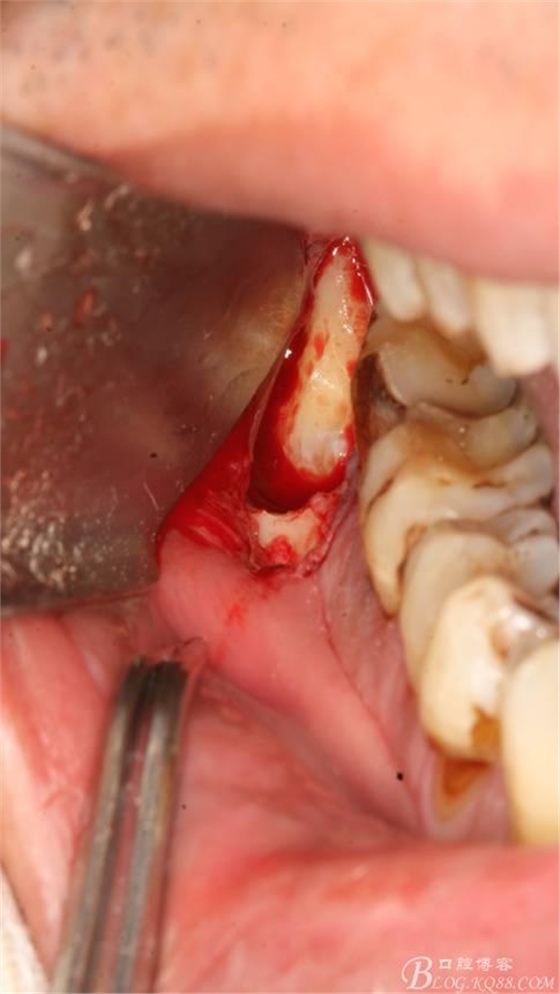

3.去骨、暴露48.

4.縱分牙根和牙冠

5.取出牙根